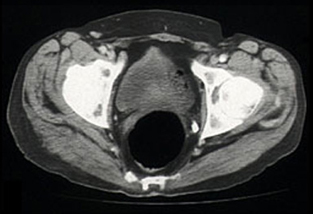

Tissue from the right gluteus medius muscle was obtained by open biopsy. Histological examination revealed diffuse infiltration of malignant lymphoid cells (Box, Figure 3), with positive immunoperoxidase staining for the leukocyte common antigens CD20 and CD79. A diagnosis of diffuse large B-cell, non-Hodgkin's lymphoma was made.

When the diagnosis was established, methotrexate was also stopped. The patient presented for CHOP-based chemotherapy (cyclophosphamide, adriamycin, vincristine, prednisolone) 19 days later (2 months after he stopped taking cyclosporin). The palpable swelling of the right buttock had disappeared, and a repeat CT scan confirmed resolution of the previously diffuse muscle swelling (Box, Figure 4). Chemotherapy was withheld.